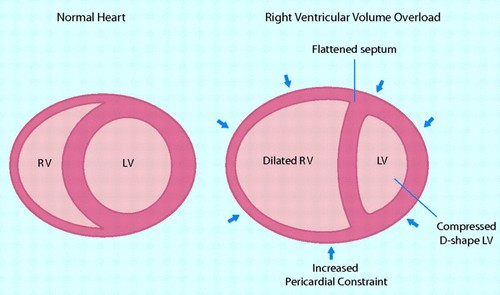

Có sự phụ thuộc lẫn nhau rất quan trọng giữa tâm thất phải và tâm thất trái. Sự phụ thuộc này thể hiện là: (1)cả hai tâm thất có chung nhau vách liên thất, (2)điểm kết thúc của vách liên thất phía trước và phía sau là thành tự do thất phải, (3) cả 2 tâm thất cùng chung nhau các sợi cơ vòng bao quanh tim và (4) cả 2 tâm thất cùng chung nhau màng ngoài tim. Khi thất phải giãn ra cấp tính, ví dụ như trong nhồi máu thất phải hoặc trong tắc động mạch phổi cấp, sẽ làm vách liên thất bị đẩy sang phía tim trái. Sự thay đổi này dẫn đến giảm đổ đầy tâm trương thất trái và giảm sức co của thất trái. Sự giới hạn của khoang màng ngoài tim là yếu tố quan trọng góp phần dẫn đến hậu quả giảm đổ đầy tâm trương ở thất này khi thất bên kia giãn ra.

Thất phải có thể chịu được tình trạng quá tải về thể tích trong nhiều năm, nhưng nó không thích nghi được với tình trạng quá tải về áp lực. Khi đối mặt với tình trạng tăng áp lực ĐMP phổi cấp, chẳng hạn như trong thuyên tắc nhánh lớn ĐM phổi, để duy trì cung lượng tim, thất phải buộc phải tăng cường lực co bóp. Tình trạng này nhanh chóng dẫn đến giãn thất phải và suy chức năng thất phải với biểu hiện lâm sàng là tụt huyết áp và sốc tim. Bên cạnh đó, khi áp lực động mạch phổi tăng lên, theo định luật Starling, thất phải giãn ra để duy trì lưu lượng tống máu. Hậu quả cuối cùng là suy thất phải, TP chuyển dạng hình cầu (cầu hóa),dẫn đến hở van ba lá và càng làm suy tim phải tăng lên. Một vòng xoắn bệnh lý phát triển và kết thúc trong tình trạng ứ trệ tuần hoàn hệ thống tĩnh mạch.

Siêu âm tim là thăm dò không xâm giúp đánh giá nhanh chóng kích thước TP, hình dạng và sự di chuyển của vách liên thất (VLT). Đường kính TP / TT> 1, kèm theo thất trái mất dạng hình cầu (dấu hiệu chữ D) là bằng chứng về sự gia tăng ALĐMP [7]. Có thể thấy hình ảnh vách liên thất phẳng (đi ngang) thì tâm trương xảy ra khi có quá tải về thể tích (ví dụ trong các trường hợp có shunt trái –phải), hoặc VLT phẳng (đi ngang) thì tâm thu khi có quá tải về áp lực, hoặc phẳng ( đi ngang) cả 2 thì tâm thu và tâm trường khi có TAĐMP nặng (gồm cả hội chứng Eisenmenger).

Hình 6. Sự phụ thuộc lẫn nhau giữa 2 tâm thất trong suy tim phải.

Sự gia tăng bệnh lý áp lực làm đầy thất phải làm ảnh hưởng đến di chuyển của vách liên thất. Do thất phải bị giới hạn bởi màng ngoài tim (mũi tên), tăng áp lực trong buồng thất phải (RV)sẽ dẫn đến sự dịch chuyển về bên trái của vách liên thất, làm thay đổi thái của thất trái (LV). Những thay đổi này góp phần làm giảm cung lượng tim do giảm độ nhạy của TT, giảm tiền gánh và giảm độ co giãn của thất trái, và cũng làm giảm đổ đầy tâm trương TT. Dịch chuyển về bên trái do hạn chế màng ngoài tim khi tăng áp lực cuối tâm trương TP và làm biến dạng mối quan hệ về hình thái bình thường giữa 2 tâm thất cũng làm suy giảm chức năng co bóp TP.(Haddad et al 2008, AHA ).